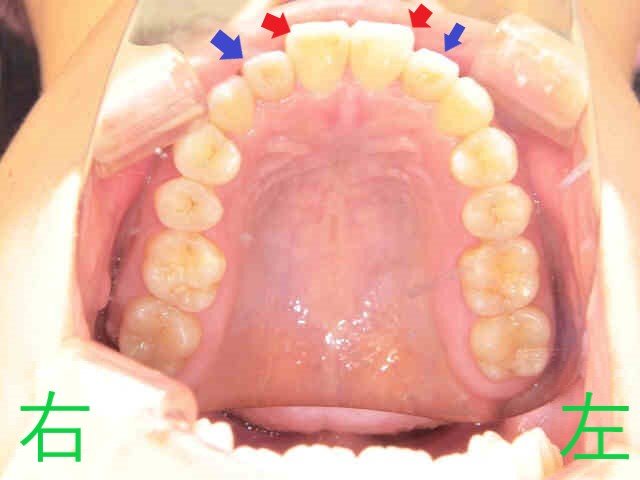

上記写真をご覧ください。

こちらは、みらい歯科・矯正歯科クリニックに勤務する歯科衛生士の口腔内写真で、マウスピース矯正(スマイルトゥルー)による治療前の様子を記録したものです。

患者本人は、以前より上顎左右中切歯(赤色矢印)の前突感(いわゆる出っ歯)と、上顎左右側切歯(青色矢印)の逆被蓋(下顎前歯より内側に位置している状態)を気にされていました。

写真は前歯の噛み合わせを下から見上げたもので、上顎左右中切歯が前方に出ており、左右側切歯が内側に位置していることが確認できます。